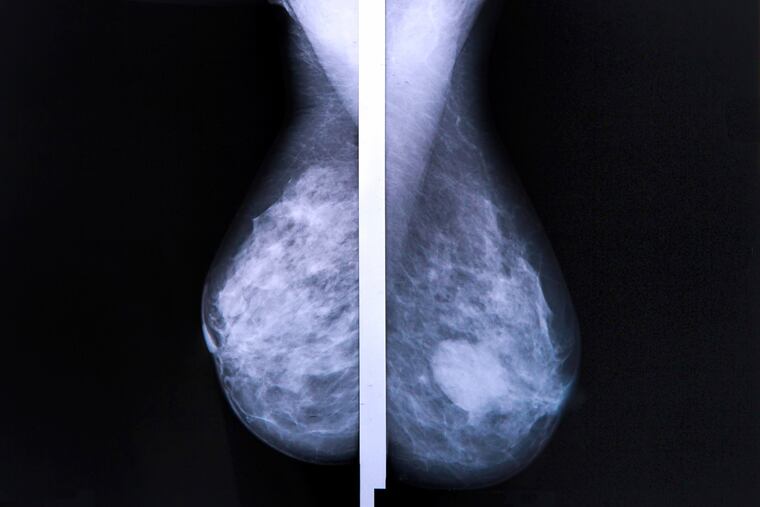

Next, observe. Due to the fact that risk of breast cancer in teenagers is so low, we can often start by observing. Fibroadenomas and cysts may shrink on their own. Sometimes a radiologic test is needed. Because teens have denser breast tissue than adults, ultrasound provides better images than mammogram. Plus, there's no radiation with ultrasound. If more information is needed, MRI is done. Again, there's no radiation.